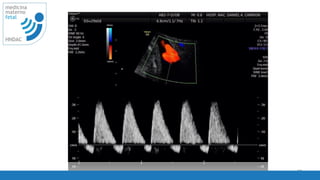

Doppler espectral

cambio de velocidad del flujo

respecto al tiempo